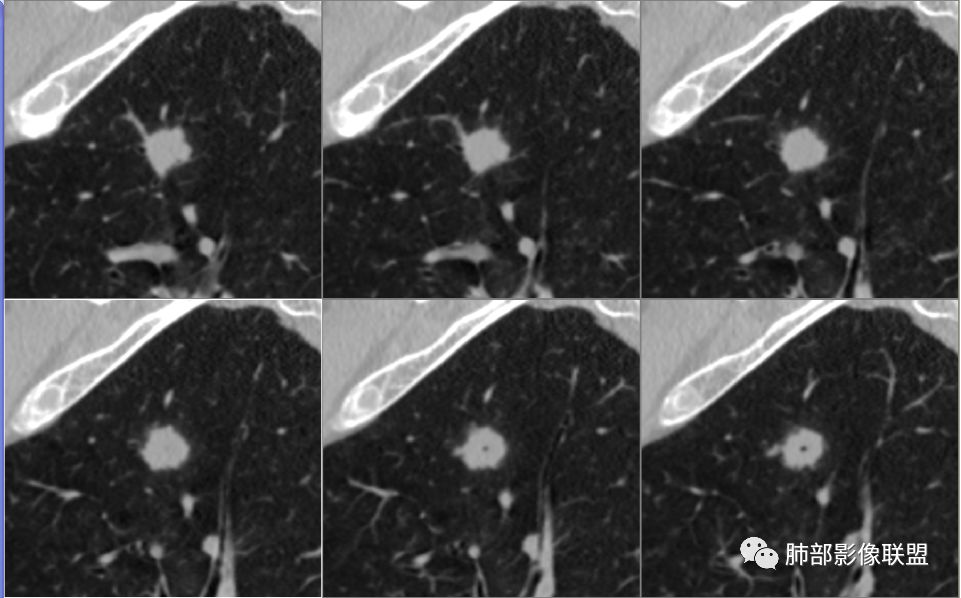

病例2资料

群内讨论

徐天鹏,宁夏海原县人民医院,放射:第二例结节局部膨隆,有血管进入,细支气管截断,考虑腺癌?

明日の路过:第二例,患者病灶在左肺上叶,分叶、空泡、血管供养征,感觉跟书上的恶性肿瘤图片一模一样。考虑恶性肿瘤可能。建议全身筛查后直接切除。

晨: 第二例,患者病灶在左肺上叶,有分叶、空泡、血管供养征,气管截断,考虑恶性肿瘤,腺癌可能。

紫气东来:病例二,结节内空泡,支气管截断,血管进入,考虑恶性。

王开金江津中心医院呼吸科:病例二,左上叶类圆形结节,分叶,毛刺,血管集束证,空泡,考虑腺癌,鉴别结核球。

欣:第二例:界清结节,有分叶,支气管截断,空泡征,腺癌,IAC

高广飞:有分叶,毛刺,空泡,腺癌?

晨读病例二,左肺上叶小结节病灶,有分叶,支气管受阻塞,中断,内可见小泡征,首先考虑恶性病变,腺/鳞癌可能。

波波:第二结节局部膨隆,分叶,空泡,细支气管截断,考虑腺癌。

晨读二:左肺上叶结节,深分叶,支气管堵塞并挤压,内部可见偏心性空泡,考虑恶性,腺癌,早期鳞癌。

大宝儿.蕊:上叶实性结节,边界清,分叶,短毛刺,小泡征,血管集束征,腺癌首先考虑。

南大分析病例2

南边:

支气管截断。

支气管在门口堵塞恶性居多,结核有时也有。

空泡

分叶

血管纠集

毛刺

总体分析,支持恶性。

应当说两例患者影像学表现都具有比较明显恶性征象,中老年男性患者,均都没有呼吸系统临床症状。

病例2肉瘤样癌的病理意见有些出乎预料,也充分说明病变及影像表现的复杂性。病灶小结节支气管截断、空泡、分叶、短毛刺、血管集束征等似乎均符合肺癌的影像特性。肺鳞癌及肉瘤样癌往往范围较小就可以出现坏死,但如果结节太小则很少能够在影像上观察到坏死区或空洞,没有增强扫描图像更是如此。